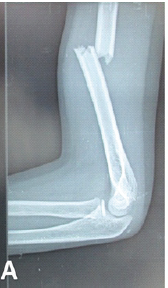

Retrograde Titanium Elastic Nailing for Diaphyseal Fractures of the Humerus in Children through a Single Central Entry Point: A Case Series with Review of Literature

Sudhir Shankar Mane , P Jayaram Reddy , Kyatham L Jagadishwer Rao